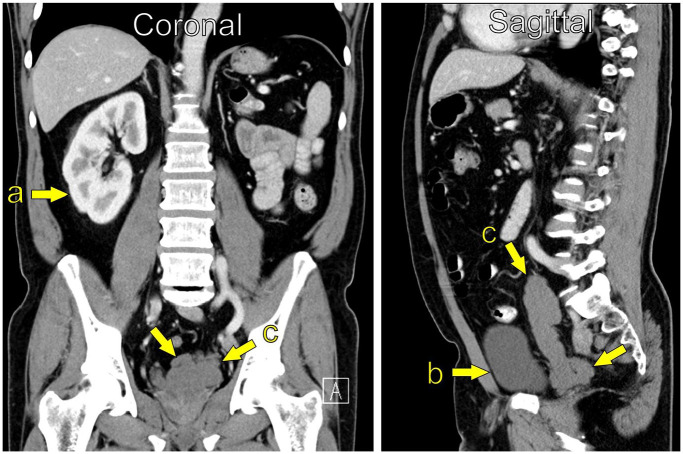

简介:Zinner综合征(ZS)以单侧肾脏发育不全、同侧精囊囊肿和射精管梗阻为特征。虽然罕见,泌尿科医生可能会遇到在他们的临床实践的某些点。文献主要局限于病例报告,对病情了解甚少。我们的目标是报告在两个中心管理的ZS病例,以便获得对这种情况的进一步临床见解。方法:对2021年1月至2024年6月期间在挪威西部两个中心出现的ZS病例进行回顾性分析。收集了有关人口统计学细节、症状学、影像学发现、管理和生育结果的数据。结果:6例患者符合ZS的全部三联征,年龄18 ~ 70岁。5例患者在出现症状时,报告诸如性活动中射精和睾丸疼痛等问题。两例急诊,一例急性尿潴留,另一例严重盆腔疼痛。半数患者采用保守治疗成功。三分之二的人通过自然受孕或辅助生殖方法生了孩子,而其余的人则接受了精子冷冻保存。结论:ZS表现出广泛的症状和不同的年龄。并非所有有症状的病例都需要手术干预,治疗应个体化。在某些情况下,保守的方法是可行的。

Introduction: Zinner syndrome (ZS) is characterised by unilateral renal agenesis, ipsilateral seminal vesicle cyst and obstruction of the ejaculatory duct. Although rare, urologists may encounter it at some point in their clinical practice. The literature is largely limited to case reports, and the condition is poorly understood. Our objective was to report on cases of ZS that have been managed at two centres in order to gain further clinical insights on this condition.

Results: Six cases were identified that met the full triad for ZS, with ages ranging from 18 to 70 years. Five patients were symptomatic at presentation, reporting issues such as anejaculation and testicular pain during sexual activity. Two cases presented as emergencies, one with acute urinary retention and the other with severe pelvic pain. Half of the patients were successfully managed with a conservative approach. Two-thirds had children, either through natural conception or assisted reproductive methods, while the remaining patients underwent sperm cryopreservation.